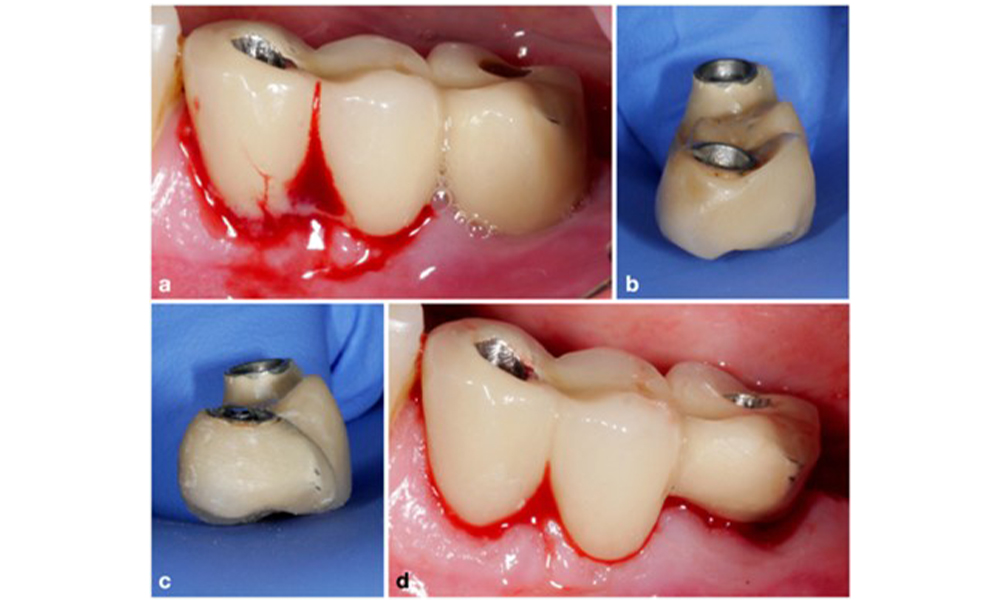

Defect extent, implant position, and its strategic importance determine whether an implant can or should be treated. Similar to a non-treatable (hopeless) implant, a severely affected implant in a multiple-unit restoration may be irrelevant for treatment, as its loss does not compromise the prosthetic restoration. Consequently, it is advisable to consider explantation either upon diagnosis or during surgical intervention (figure 8).